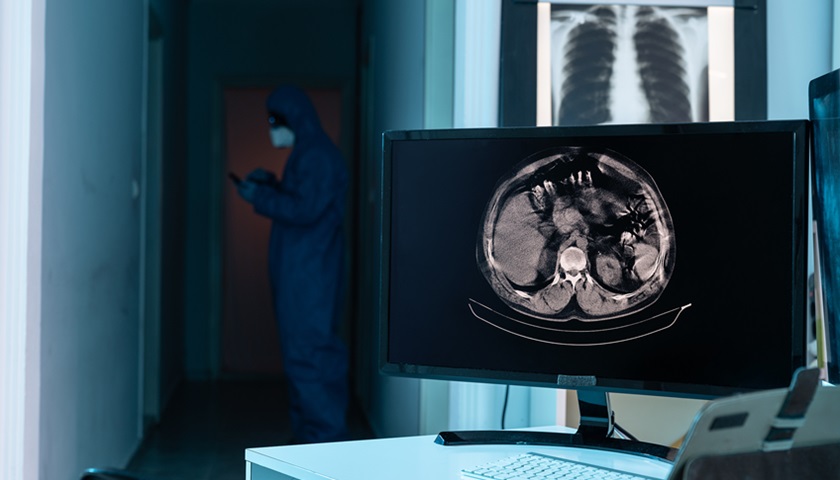

4月17日,阿里巴巴AI模型DAMO PANDA被美国食品药品监督管理局(FDA)认定为突破性医疗器械。DAMO PANDA是阿里巴巴达摩院(下称“达摩院”)研发的胰腺癌筛查AI模型。它通过精准识别平扫CT影像中的细微病灶,试图攻克胰腺癌早筛之难。

在此番获得FDA的突破性医疗器械认定之前,达摩院的这款胰腺癌检测模型PANDA(PANcreatic cancer Detection with AI)在国内已有了一定知名度。

2023年底,国际医学期刊《自然·医学》(nature medicine)刊发了《Large-scale pancreatic cancer detection via non-contrast CT and deep learning》(《基于普通CT和深度学习的大规模胰腺癌检测》)一文。前述文章介绍了PANDA模型所经历的研究,它是迄今为止经历过最大胰腺肿瘤CT训练集的模型——从20530名真实世界病患的回顾性验证发现了31例临床漏诊病变,其中2例早期胰腺癌病患已完成手术治愈。这项研究也在其申报FDA突破性医疗器械认定种发挥了重要作用。

胰腺癌是所有肿瘤中生存率最低的癌症,五年生存率仅有8.5%,素有“癌王”之称。但胰腺癌的低生存率和肿瘤的发现难高度相关——作为腹膜后的器官,由于人体腹膜后空间广阔,肿瘤在生长初期不会产生任何临床症状,直至其发展至压迫神经、患者疼痛感强烈的中晚期。这也使得尽早找到胰腺癌病灶成为了技术的突破需求。

另在影像诊断领域,普通平扫CT是临床应用最广泛的影像诊断方式,它对设备要求较低,一般体检所用CT属于此类;增强CT是静脉内注射一定剂量的含碘水溶性造影剂,然后在CT机上扫描。增强CT更有利于发现病灶,但其可及性不如平扫CT,这也使得胰腺癌病灶的发现机会被进一步摊薄。

为了实现胰腺癌早筛,达摩院的方案便是“平扫CT+ PANDA模型”。它利用了AI的能力,升级了平扫CT的诊断结果。通俗理解,在普通CT影像置入PANDA模型之后,检测者能够获得接近增强CT的扫描结果。在胰腺癌之外,达摩院也在尝试“一扫多筛”,也就是用平扫CT+AI的方式检测更多癌症、急症以及慢性疾病。